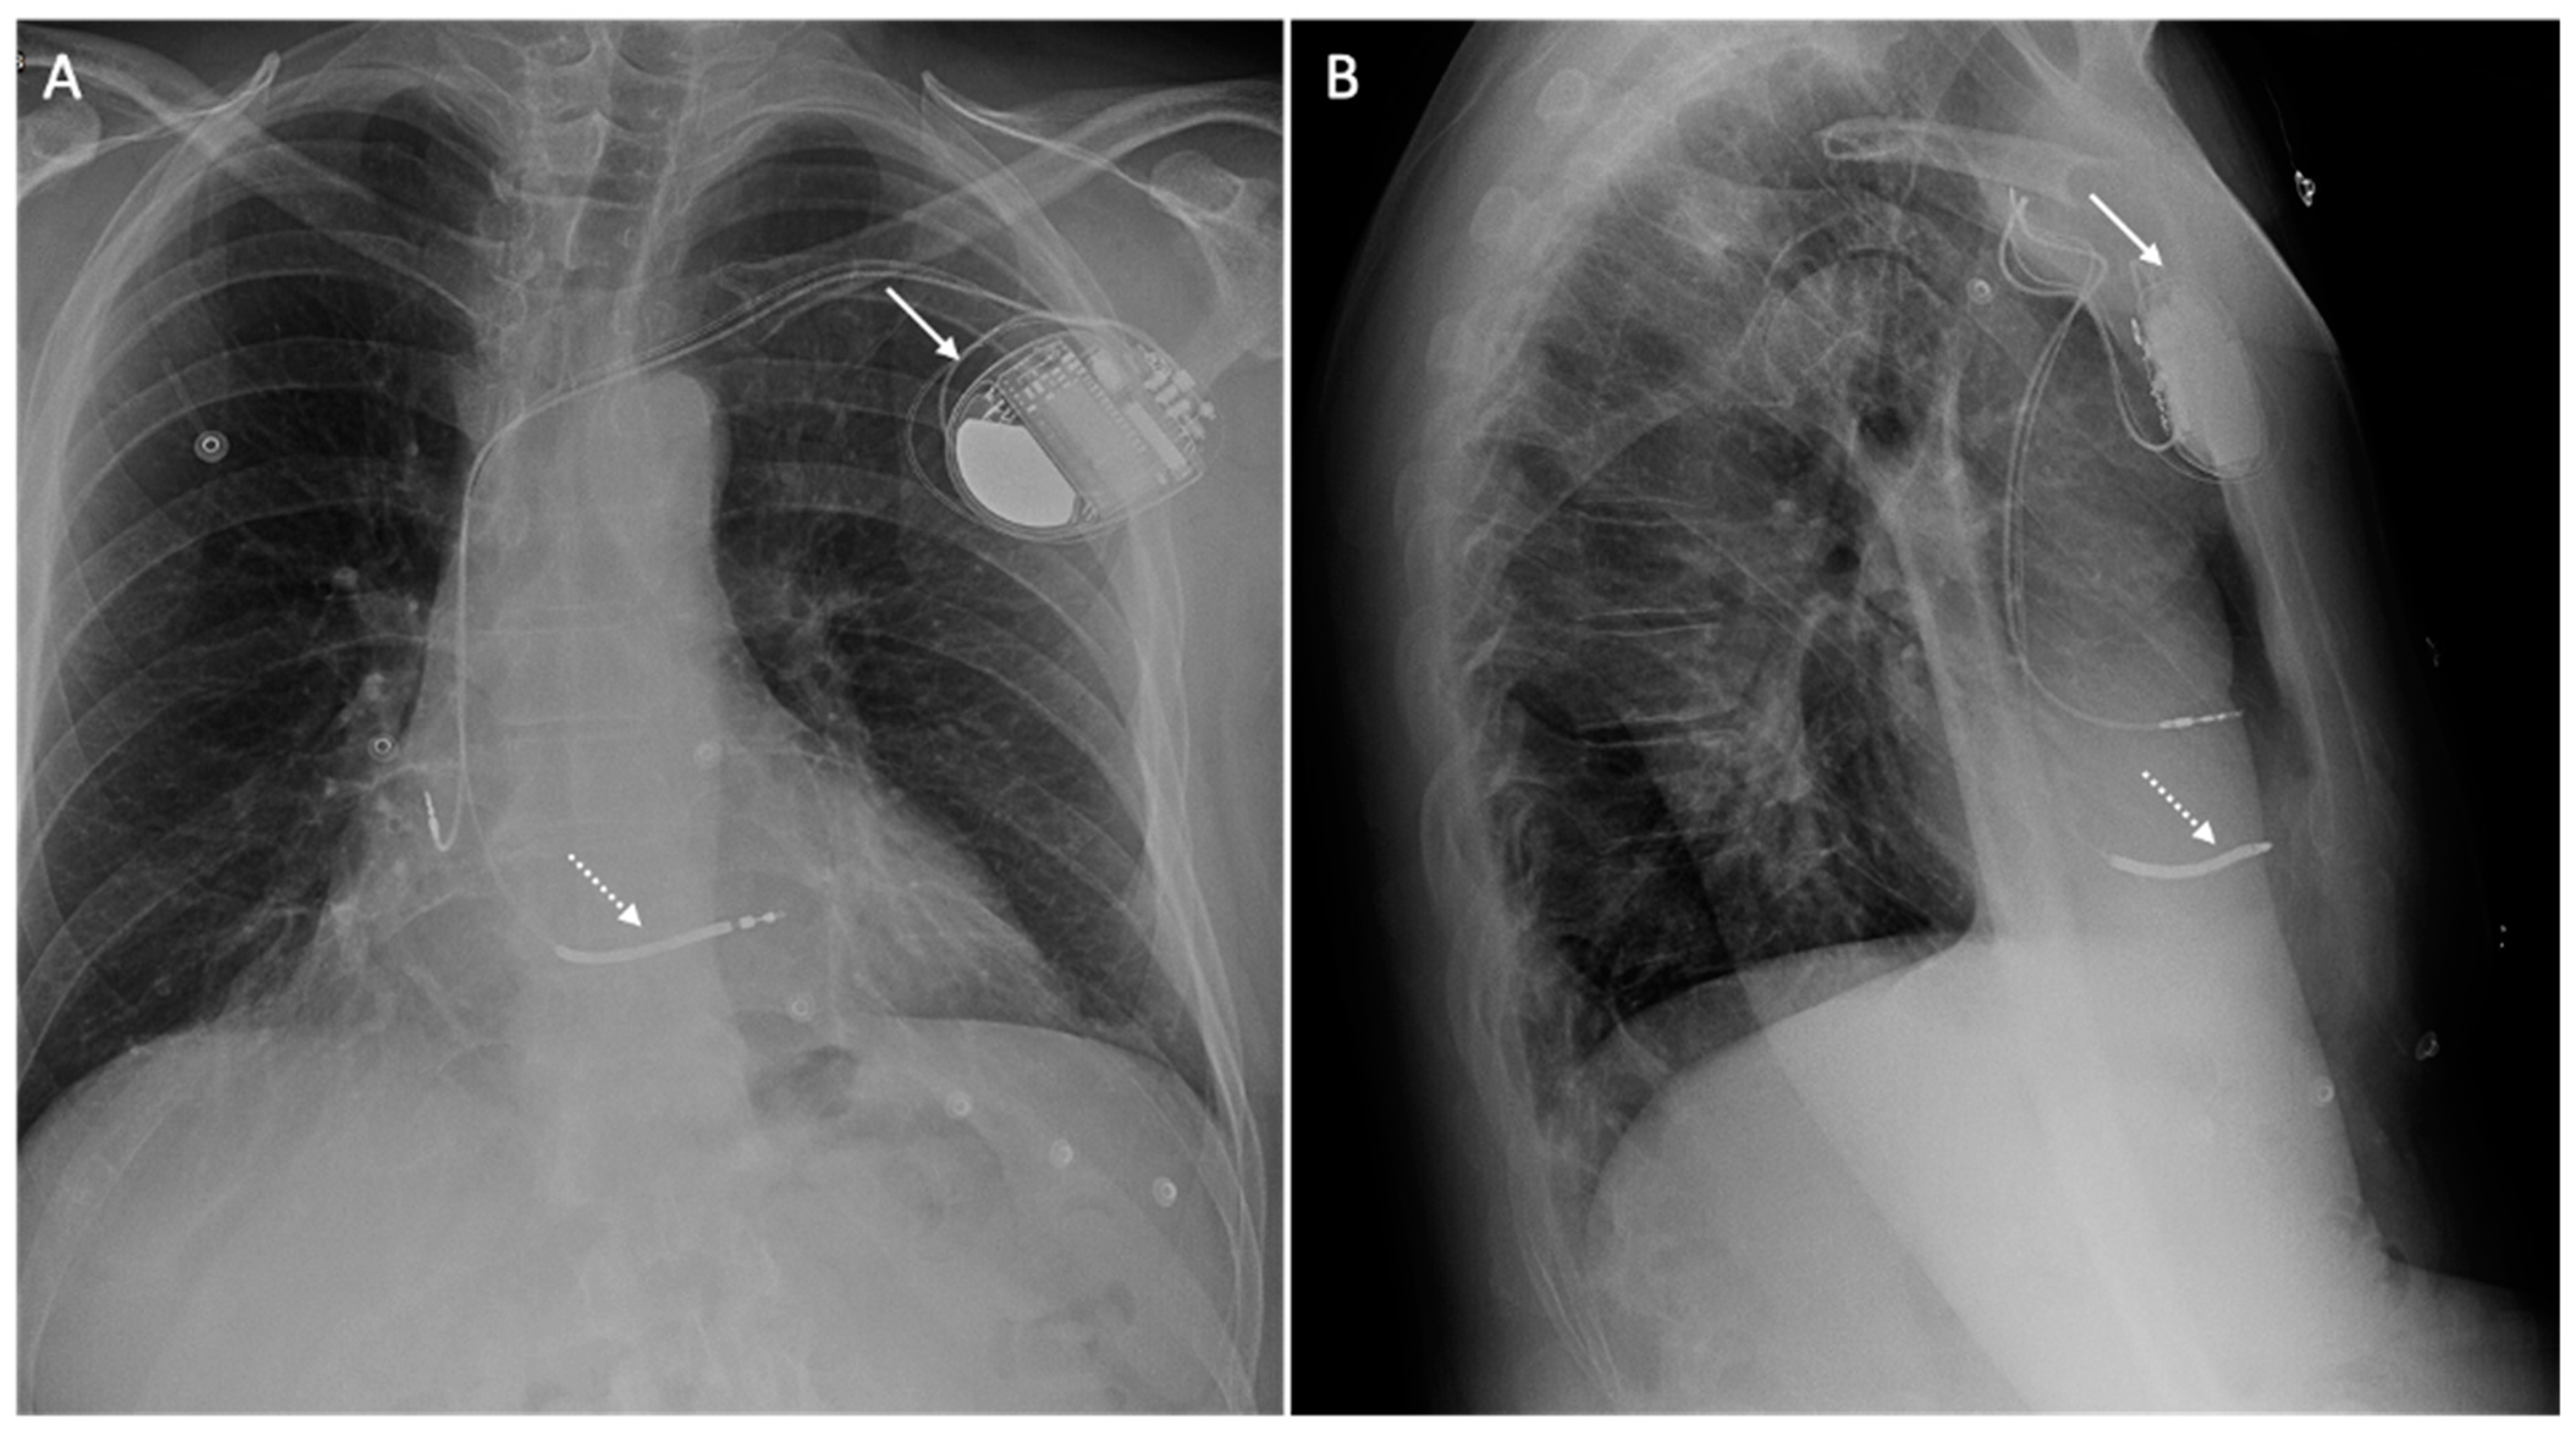

6. Issue: Artifact

- Vuorinen, A.-M.; Lehmonen, L.; Karvonen, J.; Holmström, M.; Kivistö, S.; Kaasalainen, T. Reducing cardiac implantable electronic device–induced artefacts in cardiac magnetic resonance imaging. Eur. Radiol. 2022, 33, 1229–1242. [Google Scholar] [CrossRef] [PubMed]

| Types of Artifacts | Factors that Influence Artifacts | High Artifact | Low Artifact |

|---|---|---|---|

| Signal loss artifact Hyperintensity artifact | CIED’s dimension | Large device | Small device |

| CIED’s position | Left-sided implantation | Right-sided implantation | |

| Magnetic susceptibility | High ferromagnetic component | Low ferromagnetic components | |

| High static MF | Low static MF | ||

| Distance from the region of interest | Proximity to the heart | Elevate the patient’s arm | |

| MRI sequences used | Cine SSFP | SGE sequences | |

| LGE sequence with a bandwidth of about 1 kHz | LGE sequence with a wide bandwidth |